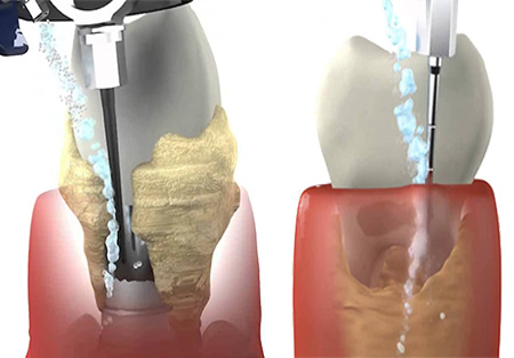

Фото и примеры имплантации зубов при пародонтите

Раздел: Необычные решения